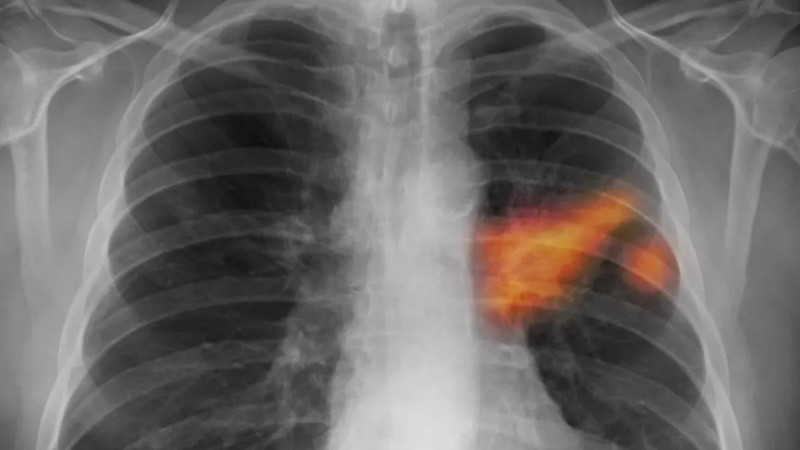

Nová studie vědců z University of Virginia Health System ukazuje, že prodělané těžké virové infekce dýchacích cest, jako covid-19 nebo chřipka, mohou zvyšovat riziko vzniku rakoviny plic, a to až o 1,24násobně, což podtrhuje důležitost sledování pacientů po vážných respiračních onemocněních stejně jako rizikových kuřáků. #rakovinaplic #covid19 #zdravotnipeci

Výzkum z University of Virginia Health System ukazuje, že těžké respirační virózy mohou trvale narušit imunitní odpověď v plicích, což zvyšuje riziko vzniku rakoviny plic, s pozitivním zjištěním, že očkování může těmto nebezpečným změnám zabránit. #rakovina #prevence #zánět

Zánět, který nahrává nádorům Tento překvapivý a zároveň varovný objev nedávno učinil tým výzkumníků z americké University of Virginia Health System (UVA).